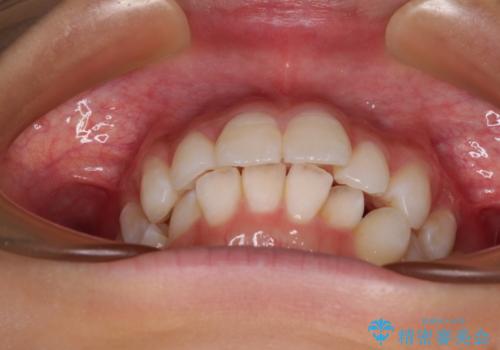

- 口を閉じたときに飛び出してしまう上顎前歯を気にして来院された患者様です。

下唇に前歯が当たって跡が残ってしまう状態でしたが、スッキリとした口元に仕上げることができました。